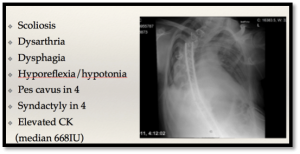

Her patients lacked the cystatin b mutation and had a severe phenotype: rapid progression of the myotonia and seizures, leak of a muscle enzyme called CK, difficulty speaking (dysarthria) and swallowing (dysphagia) and ultimately died at a young age (24 years on average). Many had musculoskeletal malformations, like the severe scoliosis seen in the X-ray of an afflicted person (above). These patients paradoxically worsened when they received common epilepsy treatments, such as phenytoin or carbamazepine. Their deep phenotype included highly photosensitive patients who had juvenile tonic clonic seizures as well as myoclonus, minimal cognitive decline and a normal electromyogram. Phenotype in hand its just a matter of sotring through the 25,000 human genes to identify a cause! They chose to use linkage analysis, a technique that identifies the chromosomal location of an unidentified disease-causing gene by tracking its known “neighbours” (satellite markers). Linkage analysis combines a deep phenotype with careful family history and monitoring the inheritance of these satellite markers as they pass through the family tree, see genome family tree.